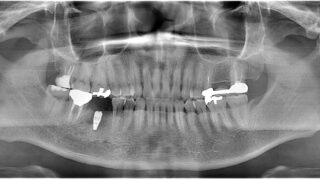

今日のインプラントオペ

今日のインプラントオペは下顎右側6番のケースです。歯根破折したケースでしたので頬側の骨がなくGBR併用。初期固定も良かったが、骨補填材を入れているので2回法にしました。特に問題なく終了。